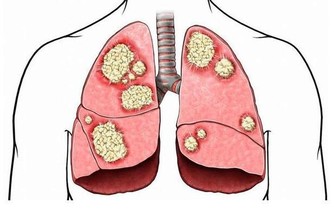

我國目前的癌症發生率,肝癌排第二,僅次於肺癌,而且大家可能都知道,肝癌的形成有三步:慢性肝炎→肝硬化→肝癌,因此,肝硬化作為肝癌來臨前的一道“重要防線”,一定要引起重視。

肝硬化是什麼?顧名思義,就是肝臟變硬了。正常的肝臟和嘴唇一樣柔軟有彈性,

而硬化的肝摸上去就如同鼻尖一樣,有韌性沒彈性,而且病程越長,肝臟就越硬。

其實肝硬化初期的癌變風險並不大,但如果持續不治療,甚至對它進行不良刺激,

肝硬化愈加嚴重,癌變的機率也會隨之增大。

儘管肝硬化的早期不適症狀並不明顯,但也可以尋找到一些肝變硬的“蛛絲馬跡”,然後及早發現,科學治療。